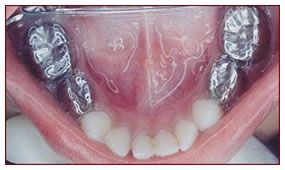

Pulpotomy ,Pulpectomy & SS Crown

All severely damaged milk teeth are saved by this procedure wherein the decayed living tissue is removed and filled with restorative material.

The teeth that are saved by this method is further strengthened by capping with metal crowns.